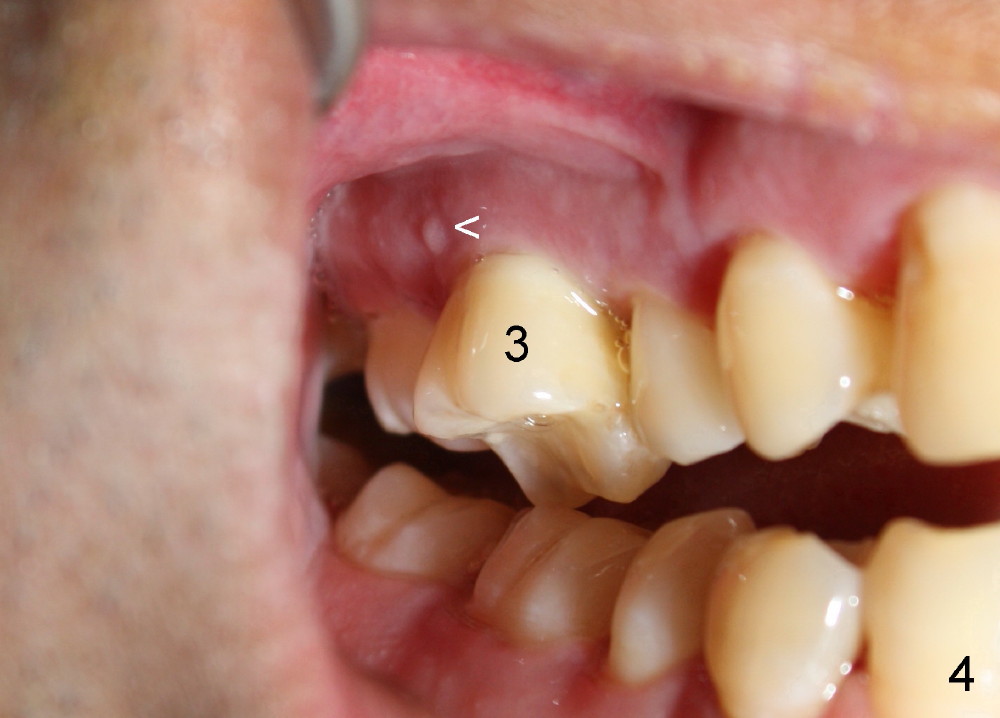

The tooth #3 has severe periodontitis with probably endodontic lesion (Fig.1,2). The patient is a 43-year-old man with apprehension of dentistry. An acute infection causes pain and tooth shift (Fig.4,5). A 7x17 mm immediate implant is planned (Fig.3). The palatal socket is shallow (Fig.6 P), corresponding to severe recessive palatal root (Fig.5 P). The osteotomy is created mainly in the buccal socket (Fig.6 B), exactly in the lingual slope of the septum. Initially osteotomes are used, followed by tap placement (Fig.7 T (4.5x20 mm at the depth of 17 mm). When the implant is placed as planned (Fig.8 I), there is more vertical contact (Fig.8 red line) than that associated with the tap (Fig.7 red line). The corresponding insertion torque is between 50 and 60 Ncm. There is only one small gap buccally, which is filled with bone graft (Fig.9 <). After the insertion of a short abutments with vertical slots (Fig.9,10 A), perio dressing is used to cover the wound. The palatal socket is expected to heal uneventfully (Fig.10 P). In fact, it does in 7 days (Fig.12 P); the bone graft in the mesiobuccal aspect is healing and stabilized (Fig.11 <). By two weeks postop, the mesiobuccal socket has healed (Fig.13 <). With removal of a diseased tooth, our body has amazing power to heal.